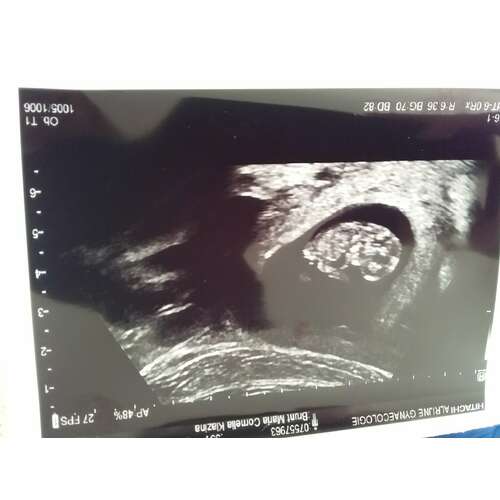

7+1 inwendige echo van onze regenboog 🌈